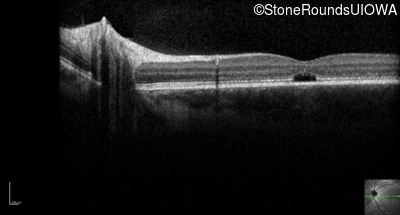

Optical Coherence Tomography - Left - 20/80 -1

Exemplar / OCT Stack

OCT Stack